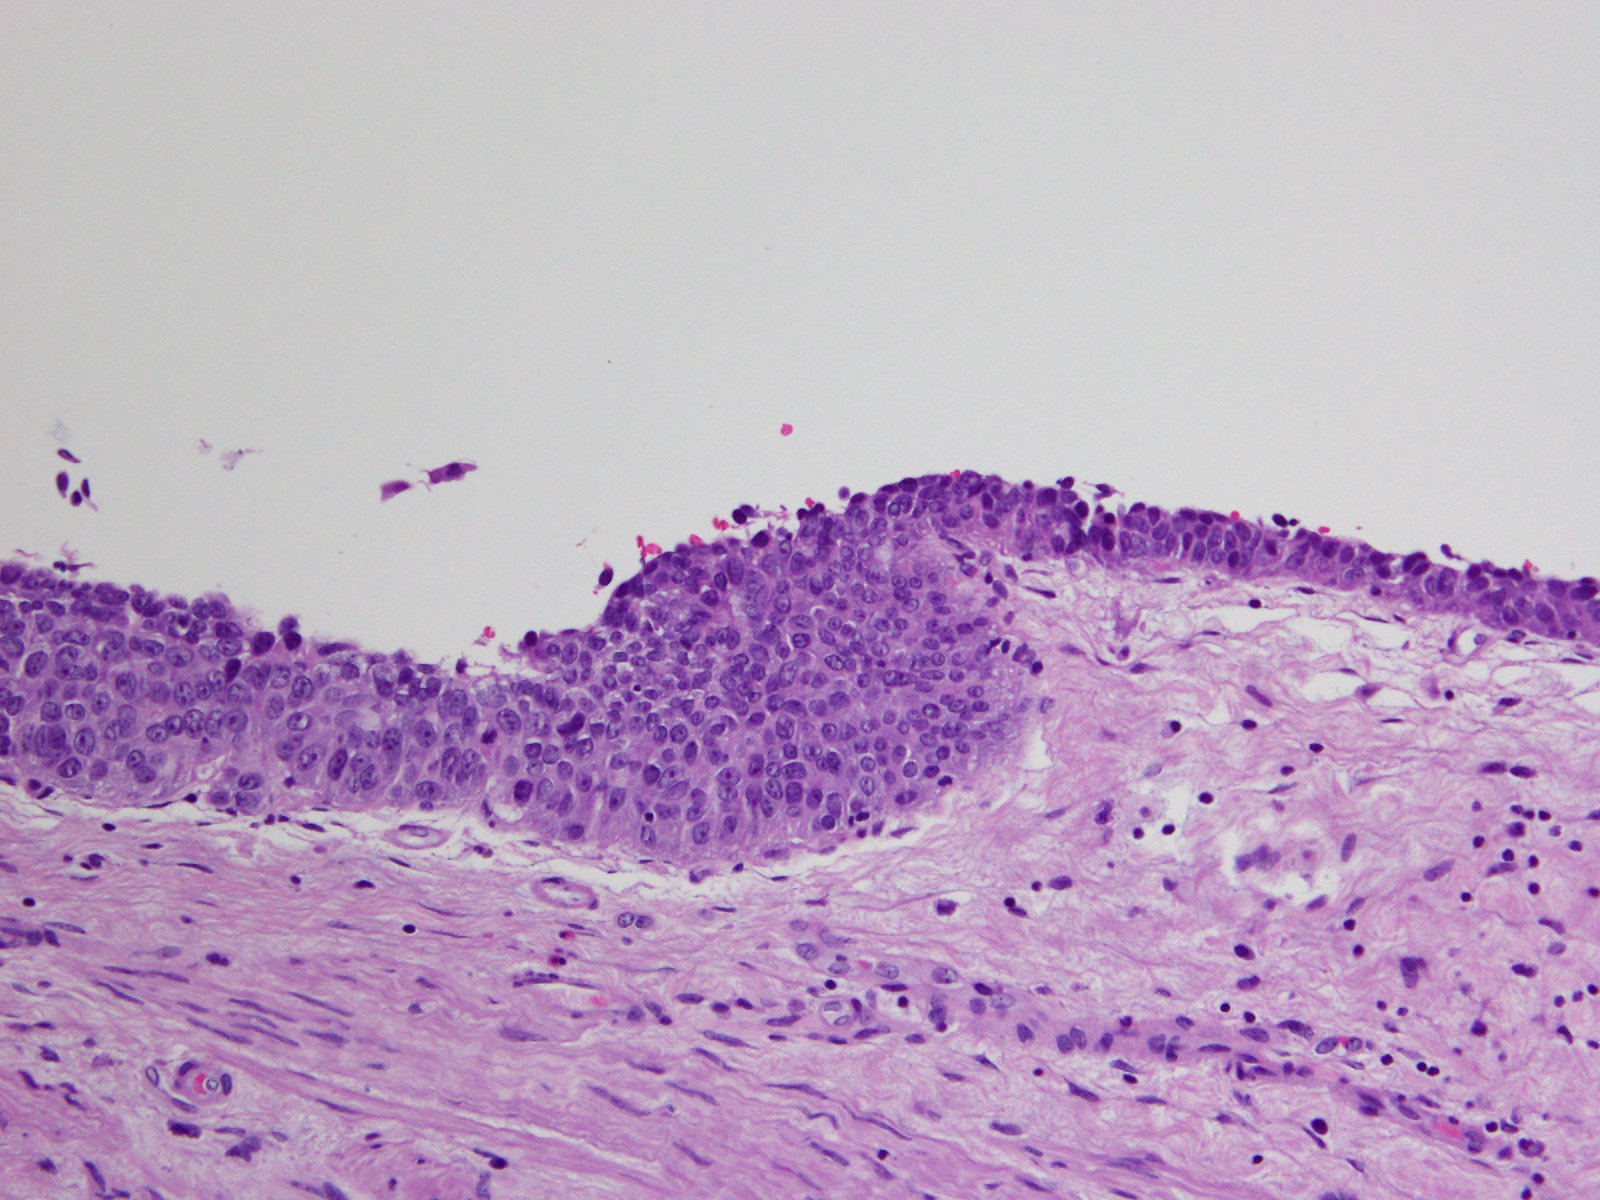

Bladder Flat Lesions

Case ID: 114

Reactive atypia

Atypia/dysplasia

Carcinoma in situ (CIS)